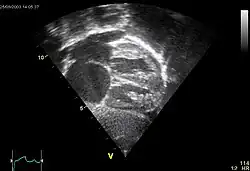

Ultrasound picture of the heart, seen in a subcostal view: The apex is towards the right, the atria are to the left. ASD secundum seen as a discontinuation of the white band of the atrial septum. The enlarged right atrium is below. The enlarged pulmonary veins are seen entering the left atrium above.